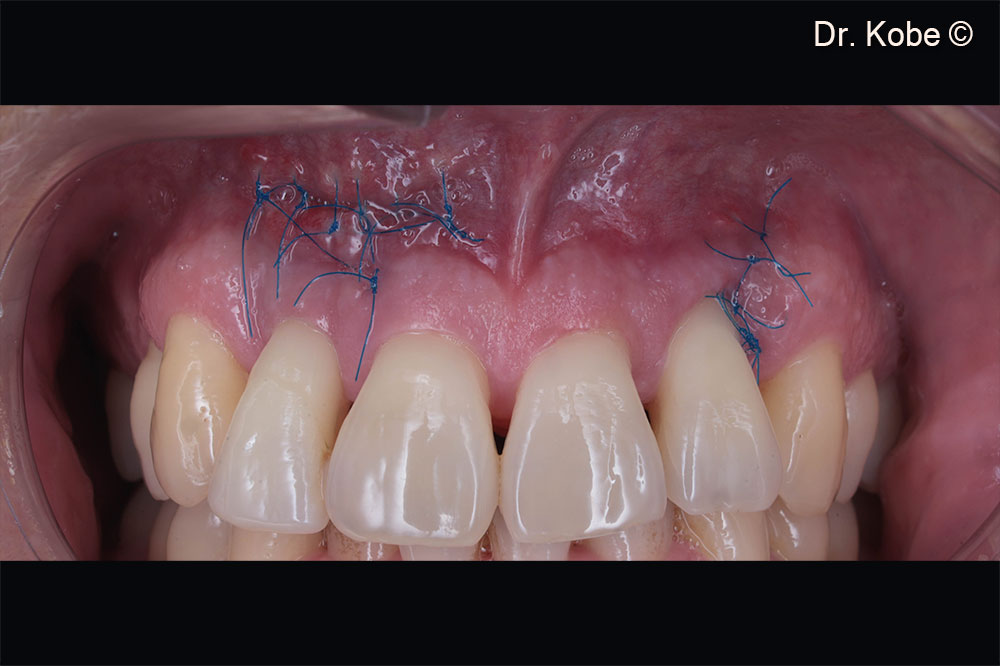

Wound sutured with interrupted sutures

Vertical incision (EPPT) at the adjacent tooth